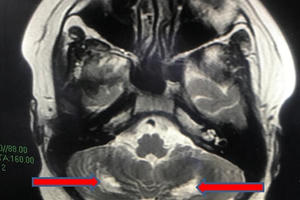

Thông tin từ Bệnh viện Nhi đồng TP HCM, các bác sĩ tại đây vừa cứu sống một trường hợp hậu COVID-19, trẻ 13 tuổi xuất hiện hội chứng viêm đa hệ thống tổn thương não.

Mắc hội chứng MIS-C liên quan đến Covid-19, một bệnh lý hiếm gặp rất nguy hiểm tới tính mạng trẻ, may mắn cháu bé được cấp cứu kịp thời.